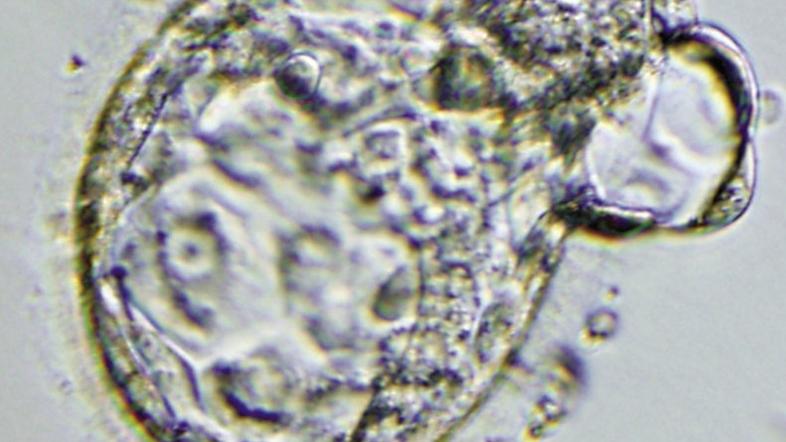

Embrio v zgodnji fazi Reuters

Na Inštitutu Francis Crick v Londonu bodo raziskovali dogajanje v prvih sedmih dnevih od oploditve jajčeca, torej od razvoja ene same celice v blastociste s približno 250 celicami. Z uporabo genske manipulacije  bodo raziskovalci poskušali zbrati nova spoznanja o našem DNK. Z novimi dognanji bi lahko tudi izboljšali kakovost zarodkov pri zunanjematerničnih oploditvah in zdravljenje neplodnosti.

Niakanova bo poskušala najti gene, ki delujejo v prvih dneh po oploditvi, ko zarodek razvije plast celic, ki kasneje postane placenta. Zarodke bodo spreminjali s tehniko, ki znanstvenikom omogoča vstavljanje, odstranjevanje in popravljanje DNK znotraj celice. Iz zarodkov se ne bodo razvili otroci, saj jih lahko uporabljajo le za osnovne raziskave in jih bodo v 14 dneh uničili. V raziskavah bodo uporabili zarodke, ki bi jih sicer uničili. Darovali naj bi jih pari, ki so bili na umetni oploditvi in jih ne potrebujejo.